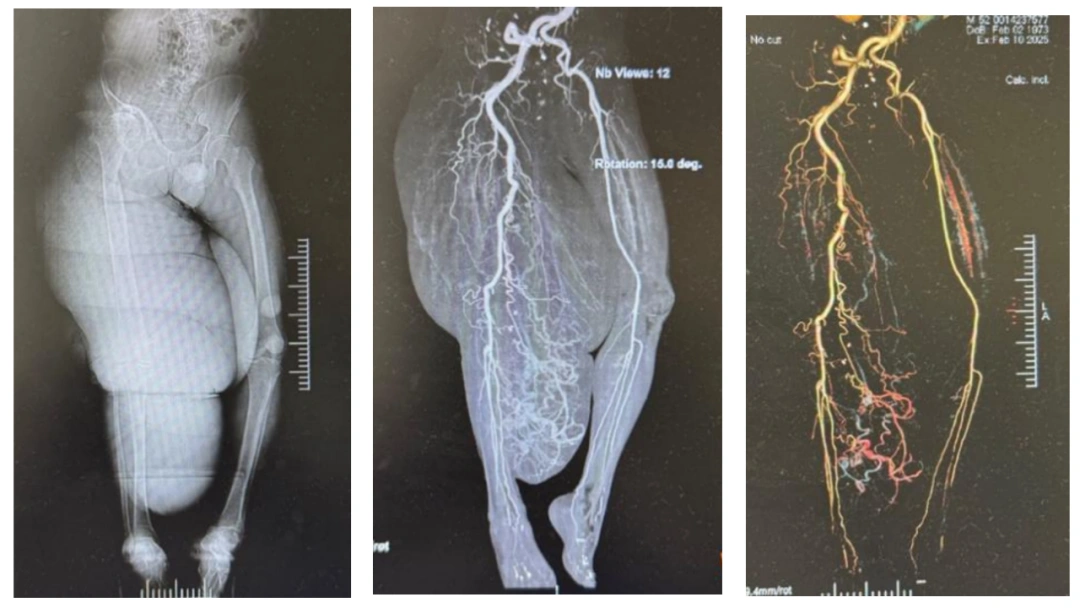

为求进一步诊治,今年2月,石先生及家人来到了中南大学湘雅医院,烧伤重建外科张丕红教授接诊了他。入院后,经过一系列检查发现,患者身体多处有咖啡色色素沉着及皮下肿块,右大腿及小腿中上段可见巨大肿块,血管造影等一系列检查显示,肿块内血管组织相当丰富,大血管窦多,且右侧股骨头缺血坏死并右髋关节半脱位、右膝关节骨关节炎。

骨科会诊表示,这些骨关节病变与右下肢肿瘤巨大超负荷活动有关,须待神经纤维瘤减容术后再行处理。这种肢体巨大神经纤维瘤,不仅影响外观和功能,而且一旦出现皮肤破损,极易引发大出血,导致休克、甚至危及生命,因此,手术势在必行。

不过,这种肢体巨大神经纤维瘤的手术难度极大,张丕红教授团队将面临三重挑战:第一,瘤体布满了血管窦腔,稍有不慎即会引发“血崩式”大出血;第二,肿瘤切除后创面修复的挑战,如果采用皮肤回植则可能皮片挛缩、影响肢体活动,若采取皮瓣法则需在尽量切除病变组织的同时,确保保留皮瓣的血供并进行良好的下肢塑形;第三,该肿瘤的复发率很高,必须切除95%以上病变组织才能降低复发风险。